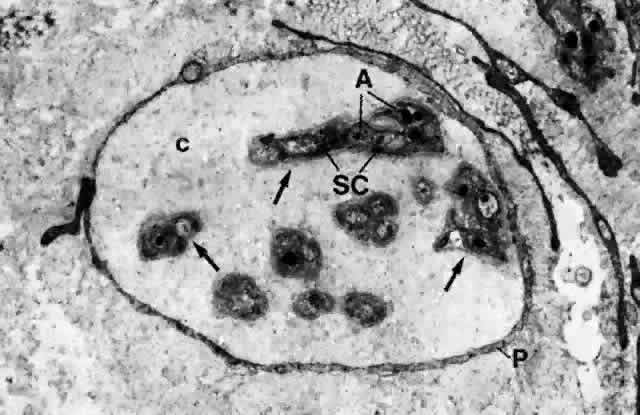

The nerve supply to the conjunctiva is derived entirely from the first division of the trigeminal nerve.10 The nerves to the lid supply most of the conjunctiva. These nerves comprise the infratrochlear branch of the nasociliary nerve, the lacrimal nerve, the supratrochlear and supraorbital branches of the frontal nerve, and the infraorbital nerve from the maxillary division of the trigeminal nerve. The limbal area is supplied by branches from the ciliary nerves. All nerves form a network in the conjunctiva and terminate either peripherally in various forms of specialized endings or on blood vessels and epithelial cells. The majority of nerve endings in the conjunctiva are free, unmyelinated nerve endings (Figs. 23 and 24). They form a sub-epithelial plexus in the superficial part of the substantia propria. Many of these fibers end on blood vessels, and others form an intraepithelial plexus around the base of epithelial cells and send free nerve endings between cells.10

Fig. 23. A nerve fiber bundle in conjunctival stroma (substantia propria) composed of several unmyelinated nerve fibers (arrows) surrounded by a layer of perineurium (P); there are also intervening collagen fibrils (c). Each unmyelinated nerve fiber is composed of axons (A) wrapped with Schwann's cells (SC). (× 13,700)

Fig. 24. Substantia propria of bulbar conjunctiva, showing myelinated (MN) and unmyelinated (UN) nerve fibers. In both fibers, axons (A) are wrapped with Schwann's cells (SC) that have a basement membrane (bm). However, the axons are single and have a myelin sheath (ms) in the former; they are multiple and have no myelin sheath in the latter. nf, neurofilament; nt, neurotubule; m, mitochondria. (× 20,800). Inset. Higher power of a portion (arrow) of the myelin sheath, showing the lamellar structure. (× 40,000)